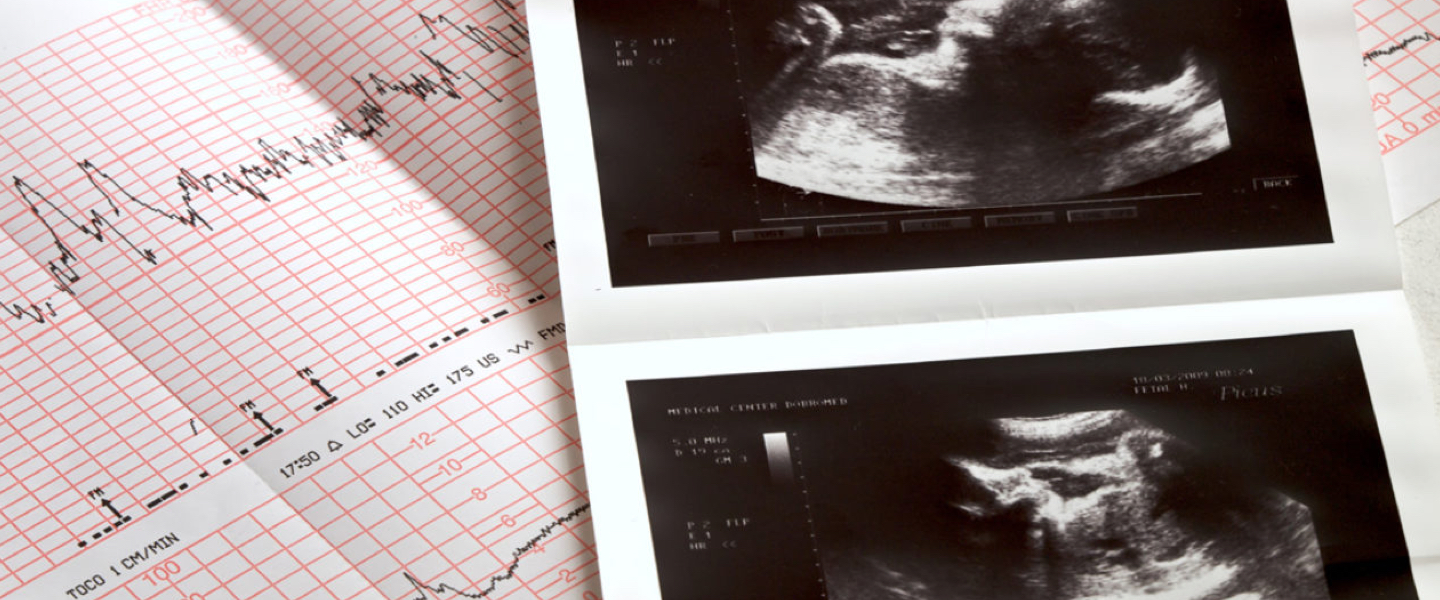

Jouw zwangerschap telt al 25 weken en met een beetje mazzel, kunnen anderen nu het hartje van je kindje horen. Heel soms lukt dit als iemand zijn of haar oor op je buik legt, maar je kunt ook een lege wc-rol gebruiken. Belangrijk hierbij is dat de rol niet wordt vastgehouden. Het is soms even zoeken naar de juiste plek. Er zijn ook speciale dopplers op de markt waarmee ook jij naar het hartje kunt luisteren.